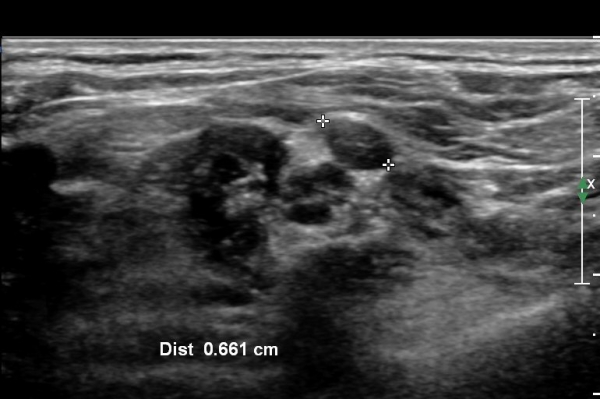

ŽÃËÀÚ¸¦ Á¶±Ý ¸»´ÜÀ¸·Î À̵¿ÇÏ¿© Àü»ç°¢±Ù°ú Á߻簢±Ù »çÀÌ¿¡¼­ »ó¿Ï½Å°æÃÑÀÇ Àú¿¡ÄÚ ºÎÁ¾ÀÌ °üÂûµÊ                  (»çÁø 2, 3).